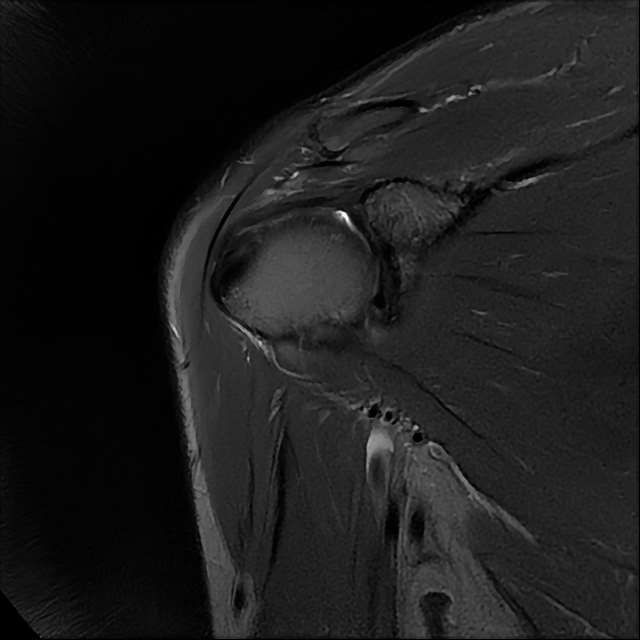

오른쪽 어깨 와순파열 및 점액낭염이 보인다고 하는데 상태를 알고 싶습니다

MRI 사진상 와순파열 점액낭염 등이 있다고 하는데..심한 상태인가요?

MRI상 와순파열, 회전근개 부분파열 등이 있으며 일부 염증소견이 있습니다.

주사, 약물, 물리치료 등에 통증이 호전을 보인다면 경과관찰을 해볼 수도 있겠지만 어깨관절의 불안정성 및 통증이 심하신 상태라면 관절경을 이용하여 수술적 치료를 받으시는 것을 추천드립니다.